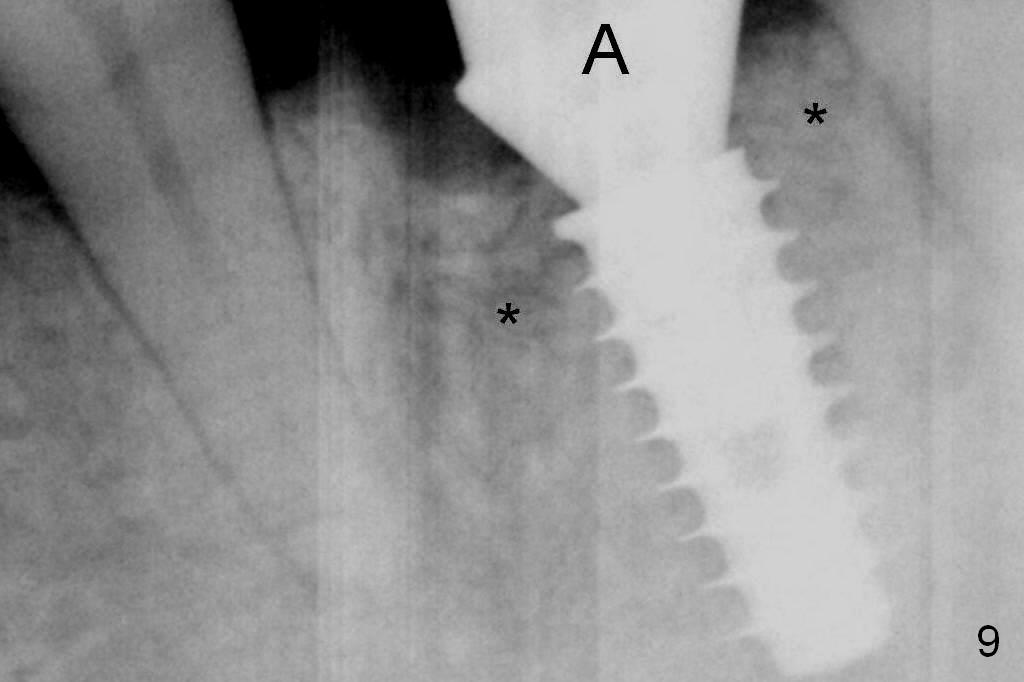

When a 5x11 mm IBS implant is being placed, the depth is tightly controlled (Fig.7). The implant is apical to the lingual crest, whereas there is ~ 2 mm implant exposure buccally clinically. That is, there is a large gap mesiobuccally, which is filled with .5-1.5 mm allograft (Fig.9 *). A 6.5x5.7(3) mm abutment (A) is placed.